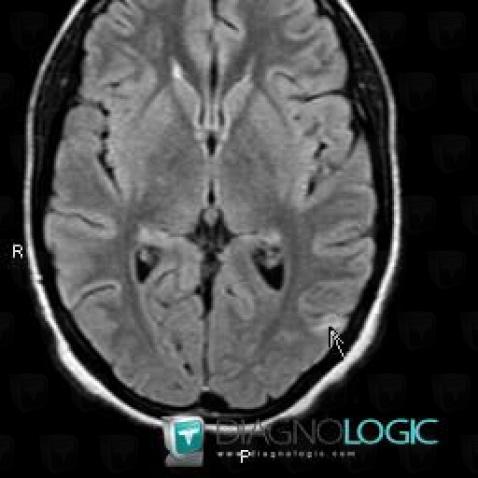

Voici les informations spécifiques à l'image clé ci dessus:

- Diagnostic Tuberculose (lié à Abcès), Localisation(s) Hémisphères cérébraux, comportant les gammes Lésion intracérébrale en hypersignal T2 ou FLAIR

Voici les informations spécifiques à l'image clé ci dessus:

- Diagnostic Tuberculose (lié à Abcès), Localisation(s) Hémisphères cérébraux, comportant les gammes Lésion intracérébrale en hypersignal T2 ou FLAIR